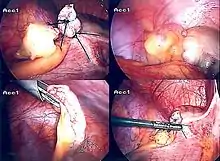

Диагностическая лапароскопия показана в сомнительных случаях, может переходить в лечебную лапароскопию при технической возможности, когда имеются условия для лапароскопической аппендэктомии; требуется письменное согласие пациента на удаление червеобразного отростка.

Постановка диагноза острого аппендицита является показанием к проведению экстренного оперативного лечения. При отсутствии явлений разлитого перитонита используется доступ Макбурнея (McBurney), иногда называемый в отечественной литературе доступом Волковича-Дьяконова. Основной этап операции при остром аппендиците — аппендэктомия (удаление червеобразного отростка).